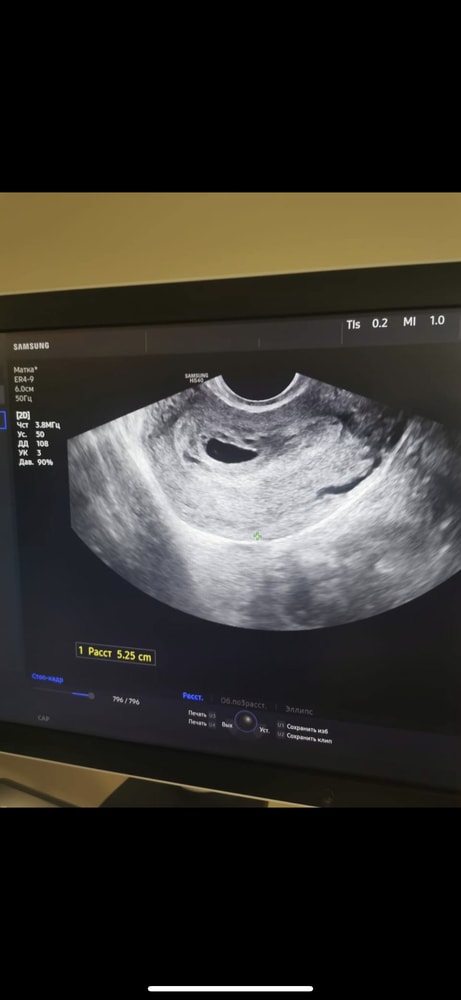

У меня не ЭКО, а естественная беременность, но тем не менее. УЗИ на сроке 5+6 недель. ПЯ 15. ЖМ 3,5. Как видите, нет эмбриона. Слова моего врача: «Всё прекрасно развивается в соответствии сроку». В срок 7+2 всё появилось. Сходила послушала сердцебиение малыша. У вас ПЯ хорошо растет, ЖМ тоже, всё развивается. Этот диагноз ставят, если плодное яйцо пустое при 25 мм, а ваш врач чуть ли на аборт не отправляет уже. 🫨 Изображение

Чудо 39, меня ещё смущает что для моего срока размер пя 13 маловато...